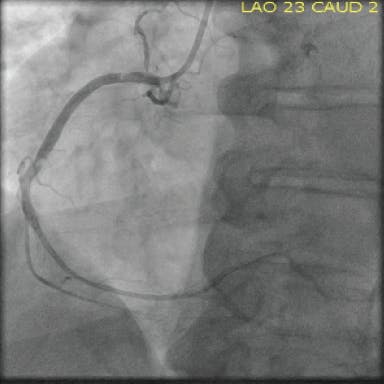

A radial approach was used for intervention. The diagnostic catheter revealed a totally occluded RCA with acute stent thrombosis and TIMI 0 flow (Figure 1). Using a whisper wire, the lesion was crossed. Two runs were then performed using CAT RX, which resulted in establishment of flow (Figure 2 and Figure 3). Subsequently, balloon dilatation was performed in the stent with a 2.5- X 20-mm compliant balloon; a 3.5- X 38-mm Resolute Onyx™ stent (Medtronic) was deployed in the mid-RCA distal to the original stent and was postdilated with a 4- X 15-mm noncompliant balloon. TIMI 3 flow was noted postprocedure, with grade 3 myocardial blush (Figure 4).

Figure 1. The occluded RCA with acute stent thrombosis.

Figure 2. Intraprocedural angiogram with CAT RX (white arrow).

Figure 3. Angiogram following aspiration with CAT RX.

Figure 4. Final angiogram with complete TIMI 3 flow after the use of CAT RX.